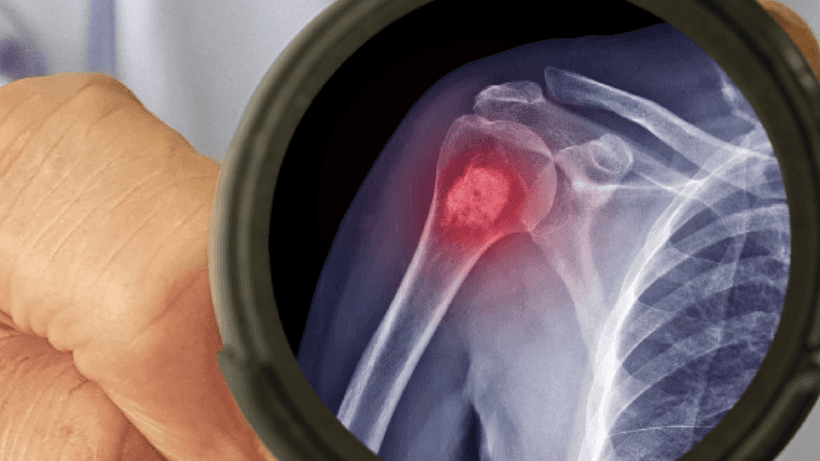

كيف يتم تشخيص سرطان العظام؟

بمجرد ظهور الأعراض وزيارة الطبيب, سيقوم طبيبك بفحصك لتحديد المشكلة ويوصي بإجراء اختبارات مختلفة للتأكد من تشخيص سرطان العظام مثل الأشعة السينية ومسح العظام وخزعات العظام, الأشعة المقطعية, إلخ.